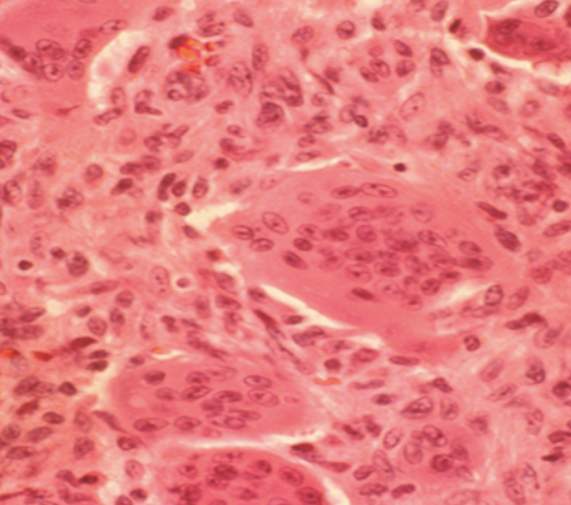

Describe the histology of GCT?